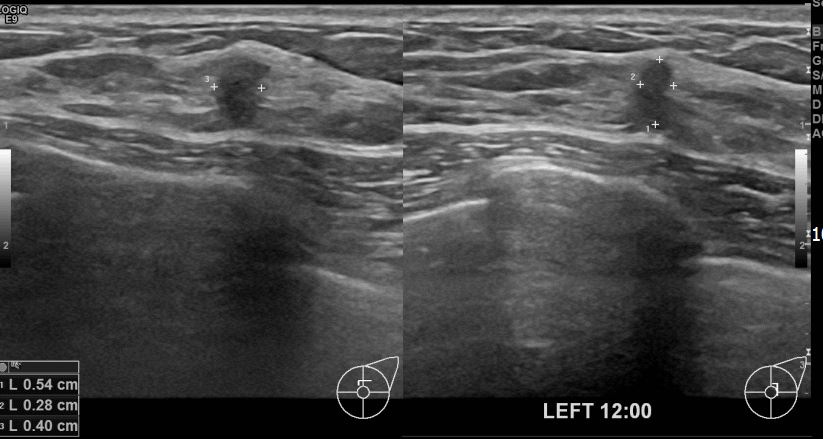

아산유외과 개원후 629번째 유방암 진단

상기 환자 외부검사상 이상소견으로 내원하신 40대 여성으로 좌측에 의심스러운혹있어 조직검사 시행후 좌측 유방암 진단되었습니다.